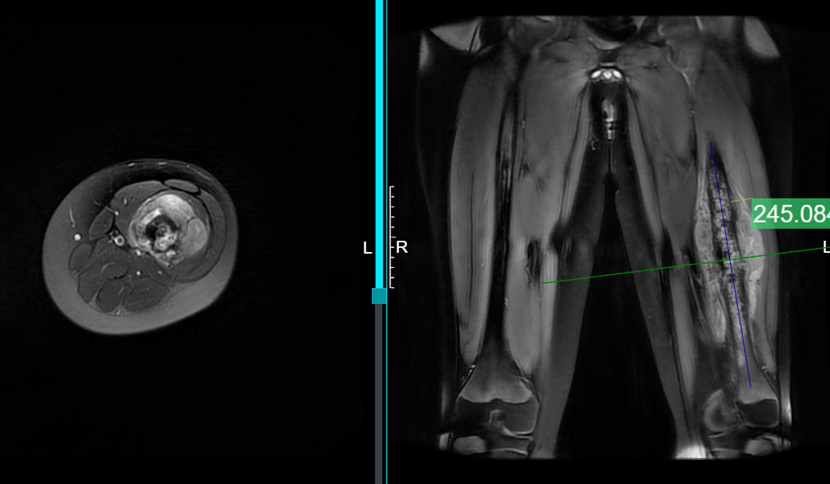

• MRI:肿瘤范围约24cm,突破骨皮质,软组织肿块明显但未明显侵犯神经血管束

• 全身骨扫描及胸部CT:未见明确远处转移